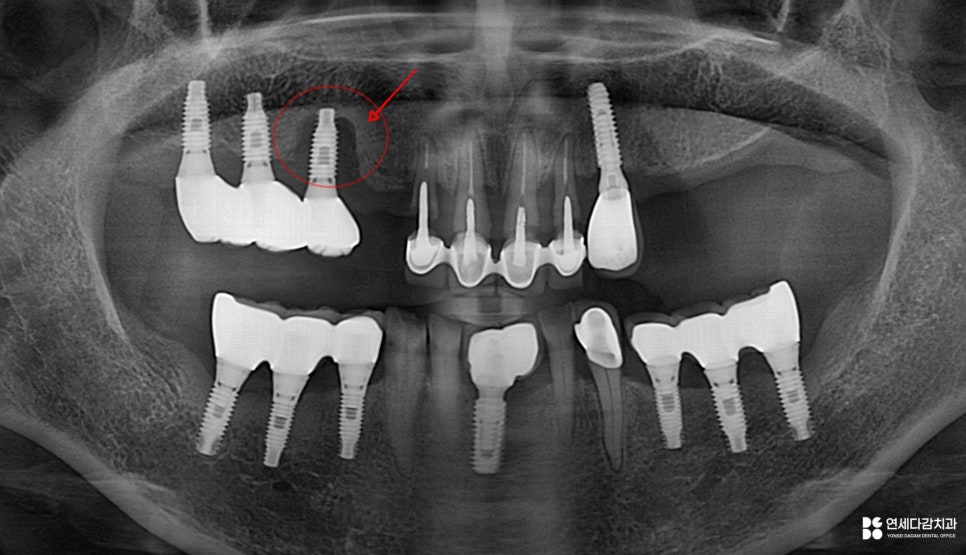

이 사진에서 제일 눈에 띄는 것은

잇몸이 상당히 내려가 있다는 점입니다.

앞니에는 보철이 수복되어 있는데

치근이 외부로 드러나 있고

그 안쪽으로는 충치까지 진행되었습니다.

25.11.18

또한 옆에 식립된 임플란트도 마찬가지로,

골소실이 굉장히 심각한 것으로 평가됩니다.

이러한 상황의 주요 원인은

바로 소홀한 청결 관리입니다.

앞서 문정동 치과 에서 언급한 치아들은

이미 유지력을 잃은 상태로써

보존은 어려울 것으로 판단됩니다.

해당 구강의 기능, 심미성을 회복하려면

임플란트를 고려해 볼 수 있는데,